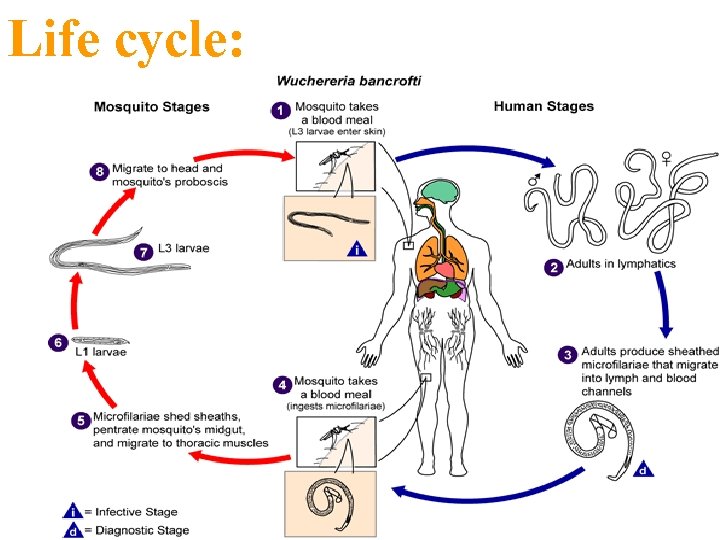

Life cycle:

Filariae: A- Wucheraria bancrofti: sheathed microfilaria; short cephalic space long tail; aseptete nuclei.

Giemsa s. Wuchereria bancrofti Microfilaria in blood smear 210 – 320 X 7. 5 – 10 µm, Note : blood collected between the hour 10 – 2 at night, this microfilaria detected in blood after 6 mouth of infection

Adults of W. bancrofti. The male worm is on the left; the female is on the right.